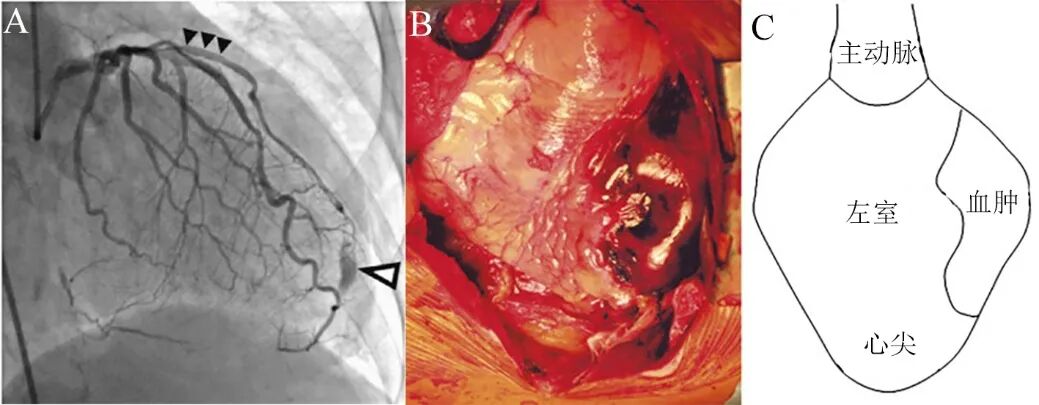

图4 心肌壁内血肿的大体观[5]。

桥血管PCI后出现壁内血肿,进行性增大,临床疑诊包裹性心包积血。但最后尸检证实为左室侧壁心肌内囊袋样血肿(A),清理血块后发现心肌夹层撕裂范围极大,几乎包绕左室游离壁(B)。